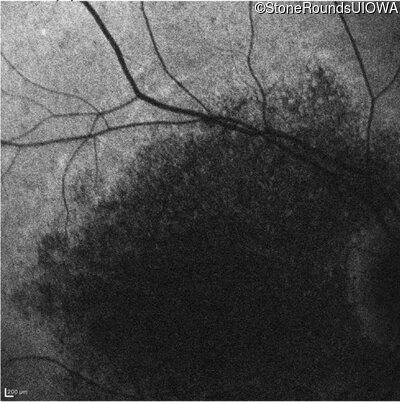

Infrared Fundus Photograph - Right - 10/125 -2 sc

Exemplar